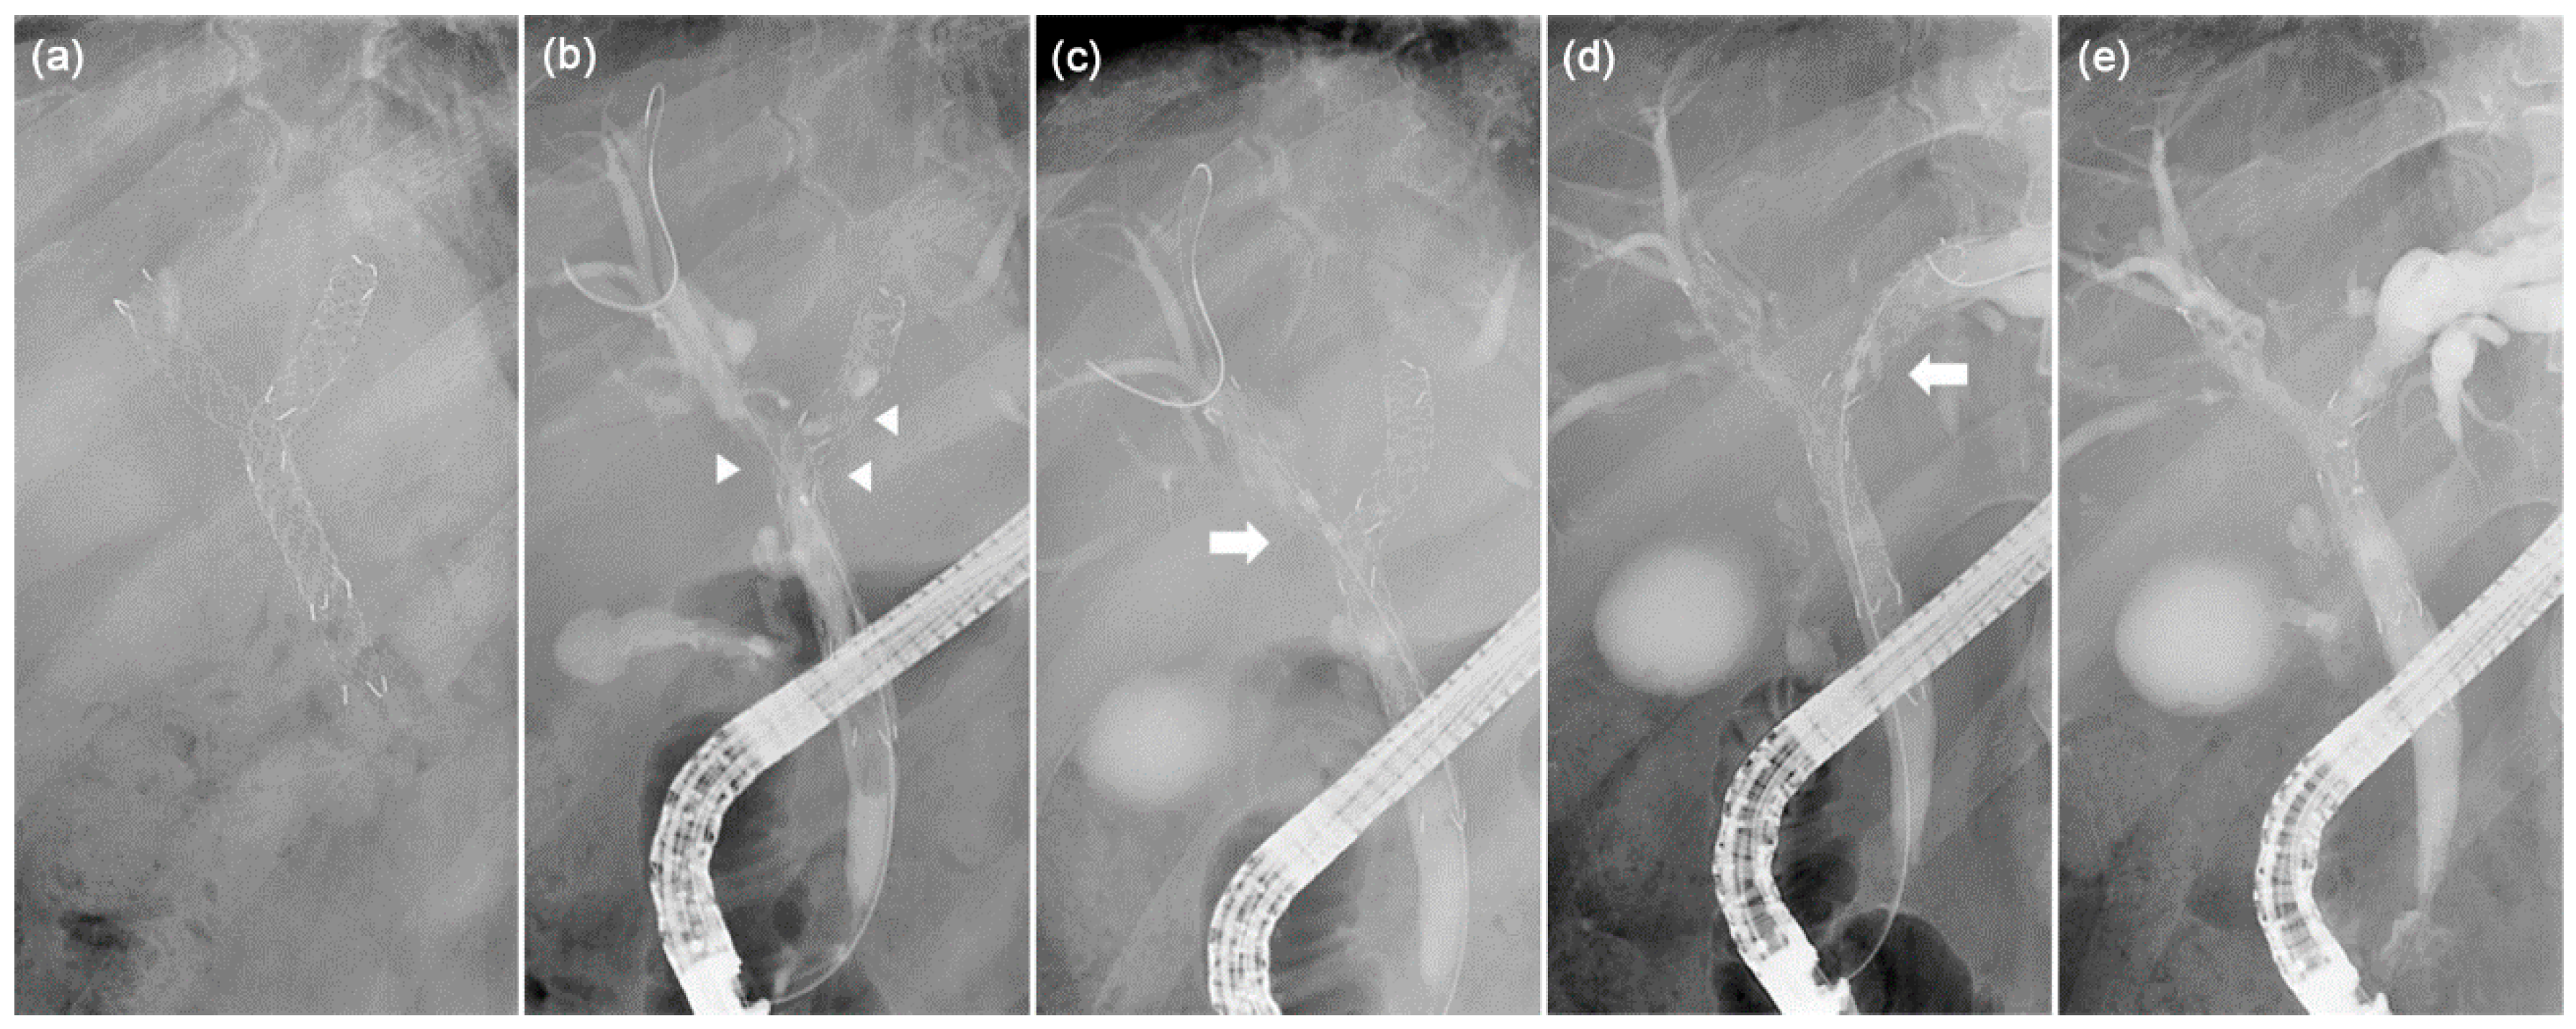

3.1. RFA Catheter and Power Settings

3.2. Endoluminal RFA Procedure